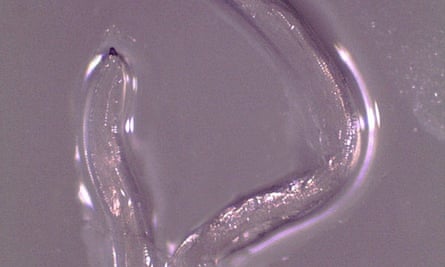

Eye worms

In another stomach-turning first, a woman in Oregon was discovered to have a type of eye worm previously only seen in cattle in 2018. The worm larvae are picked up and spread by flies which feed on cow tears.

After horse riding in Gold Beach in an area where cattle are farmed, the woman, 26, experienced a week of eye irritation. The cause was discovered when she pulled a small worm from her left eye. She sought medical help, and 14 worms were subsequently removed,most of them by the patient herself.

The tiny worms, each less than a centimetre (half an inch) long, were found to be of a species called Thelazia gulosa.

Dr Richard Bradbury, the lead author of the study that reported the case and who works with the Centers for Disease Control and Prevention’s division of parasitic diseases and malaria, said at the time that the infection was rare.

“Infections from Thelazia worms mostly happen in animals and humans are just incidental hosts,” he said. “This is incredibly interesting and I’m sure it might make some people squeamish, but it’s not something people should worry about.”